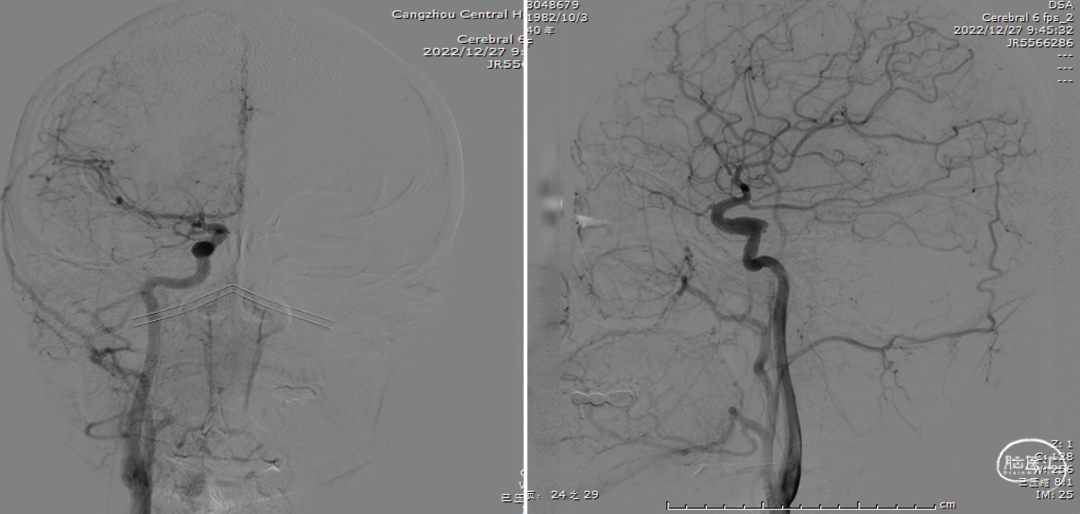

术后复查右颈内动脉造影(2022-12-27)

术后复查右颈内动脉3D重建

复查左颈内动脉造影(2022-12-27)

术后3D重建